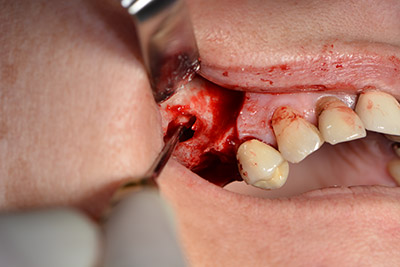

The classic incision (crestal, buccal relief) and the preparation of the mucoperiosteal flap enabled a good overview.

Sky implants (bredent) were used in this case. The surgical protocol of these, specify pilot drilling at about 1200 rpm (Fig. 9).